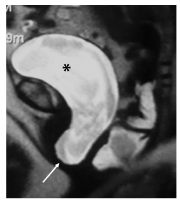

Fig. 29.2. IRM en poussée dans le plan sagittal.

Cystocèle avec importante bascule postérieure de la base de la vessie (∗) et descente du moignon vaginal entraîné par la cystocèle (flèche).

Source : CERF, CNEBMN, 2022.